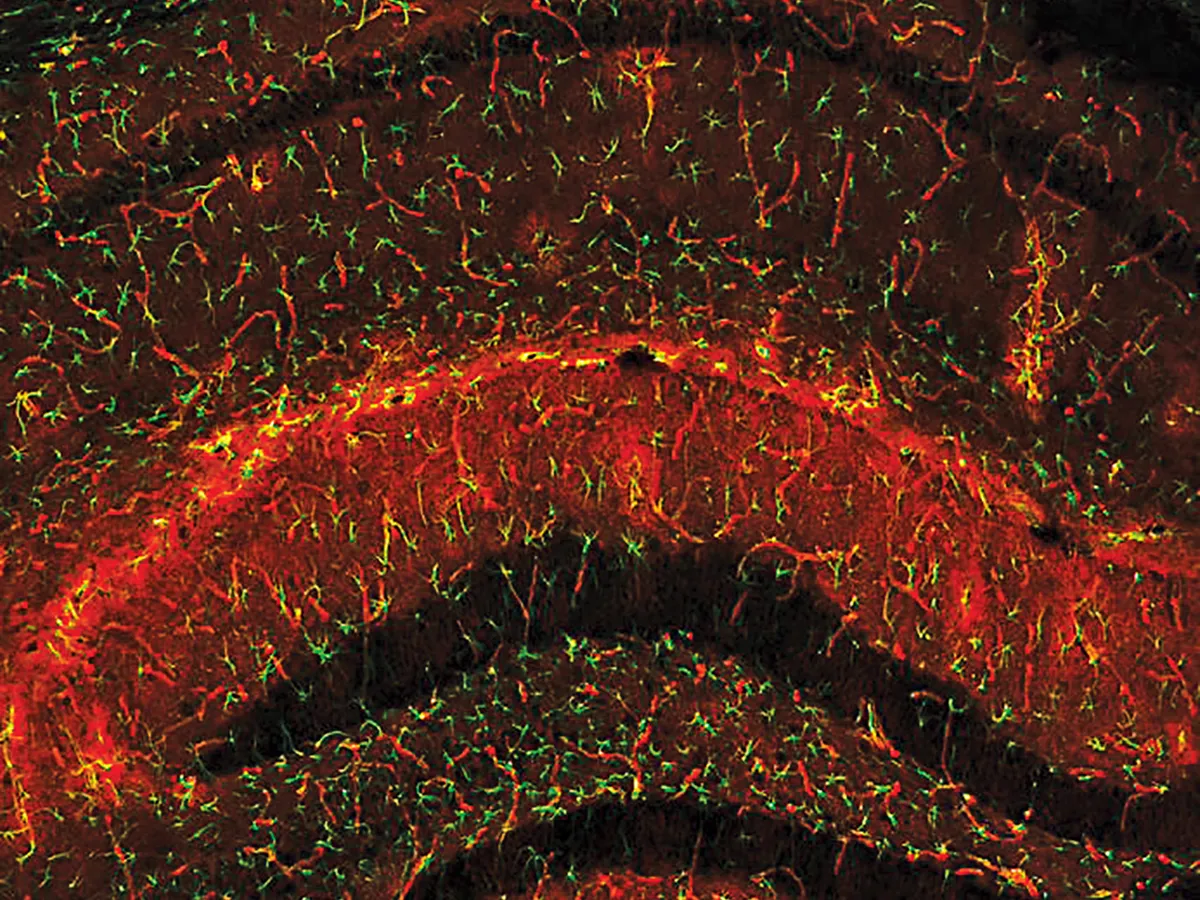

Îmbătrânirea poate fi oprită. Miliarde de dolari sunt cheltuite pentru cercetare

Silicon Valley cheltuie miliarde de dolari pe proiecte care urmăresc să blocheze procesul de îmbătrânire și, în acest proces, să evite cele mai devastatoare boli